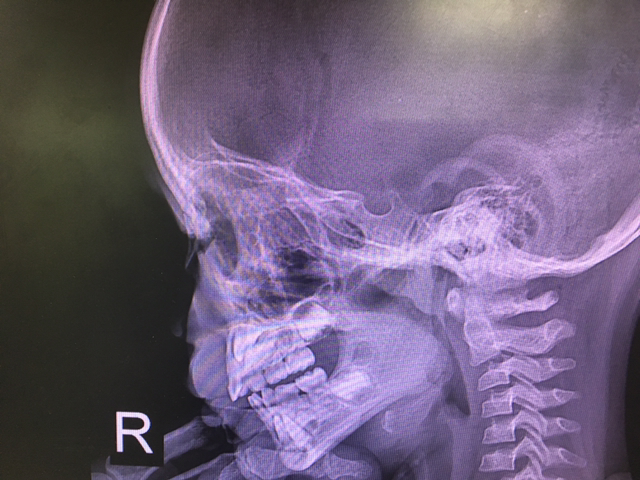

네 살배기 민경이. 의자에서 뒤로 넘어져 책상에 머리를 부딪혔다. 검사 결과 다행히 출혈과 골절은 보이지 않았다. 뇌진탕 진단 하에 부모님 안심시키며 엑스레이 사진 보여주다 방긋 웃었다. 평소엔 보이지 않던 게 보인 탓이다. 유치 밑에서 때를 기다리는 영구치가 뜻밖에 날 압도했다. 파릇한 희망의 상으로 읽혔다.